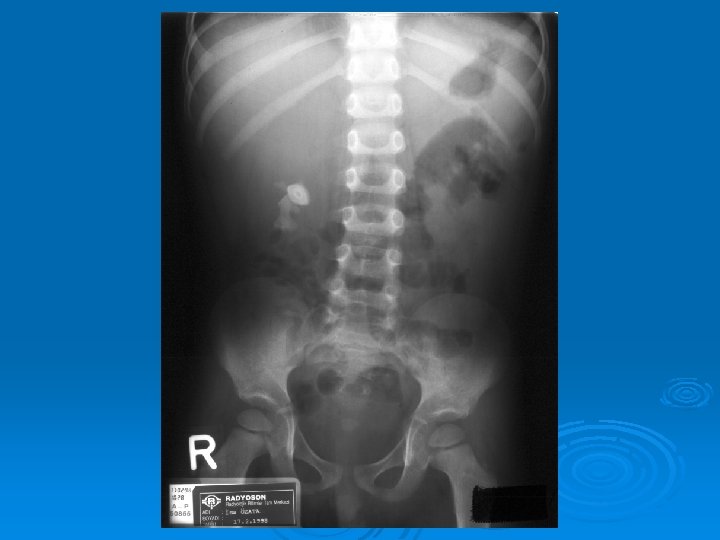

Çocukluk Çağında İdrar Yolu Enfeksiyonları İZLEMDE GÖRÜNTÜLEME GEREKEN HASTALAR Akut pyelonefrit (tüm yaş grupları) 1 yaş altı çocukta bakteriüri Erkek çocukta tekrarlayan sistit İYE ve hipertansiyon Doğuştan orta hat anormalliği

Çocukluk Çağında İdrar Yolu Enfeksiyonları İZLEMDE TANISAL GÖRÜNTÜLEME YÖNTEMLERİ Ø Miksiyon sistoüretrografisi: Vezikoüreteral geri kaçış (VÜR) görüntülenir. Ø DMSA sintigrafisi: Skar görüntülenir. Ø IVP: Tıkanıklık görüntülenir. Ø DTPA sintigrafisi: Tıkanıklık, böbrek fonksiyonları bozuk hastalarda atılım fonksiyonlarını değerlendirilebilir.